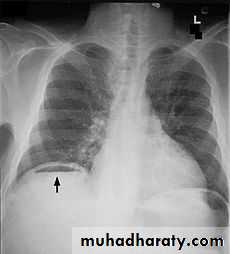

Pneumoperitoneum

Defined as free gas in the peritoneal cavityThe commonest cause is perforated peptic ulcer and two-thirds of such cases are recognizable radiologically

Pneumoperitoneum under the right hemidiaphragm is usually easy to recognize, but free gas under the left hemidiaphragm is difficult to recognize because of the overlapping gas shadows of the stomach and splenic flexure.

Gas under the diaphragm is much easier to diagnose on an erect chest film than on an upright abdominal film